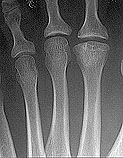

Alternatively, avascular necrosis can result from a low-grade repetitive trauma.  Examples of this are a long-term use of high heeled shoes that causes a slow, gradual death of a bone through repetitive trauma called "Freiberg's Disease" (See below).

Freiberg's Disease:  Note the flattened portion of bone to the right, compared to the other, more rounded bones on the left.